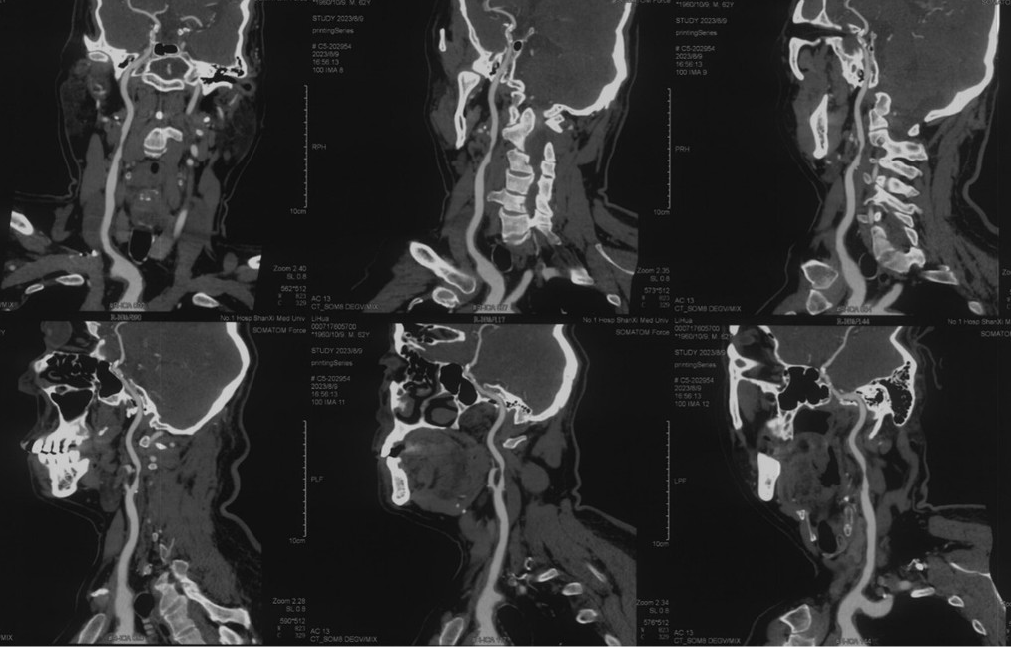

辅助检查(颈部血管彩超、CTA)

波科支架怎么样径技-弓上病例大赏|第210期·右侧颈内动脉球囊扩张术+支架植入术_https://www.jmylbn.com_新闻资讯_第6张

超声印象:

• 双侧颈动脉内膜增伴斑块形成

• 右侧颈内动脉中段狭窄

波科支架怎么样径技-弓上病例大赏|第210期·右侧颈内动脉球囊扩张术+支架植入术_https://www.jmylbn.com_新闻资讯_第7张

波科支架怎么样径技-弓上病例大赏|第210期·右侧颈内动脉球囊扩张术+支架植入术_https://www.jmylbn.com_新闻资讯_第8张